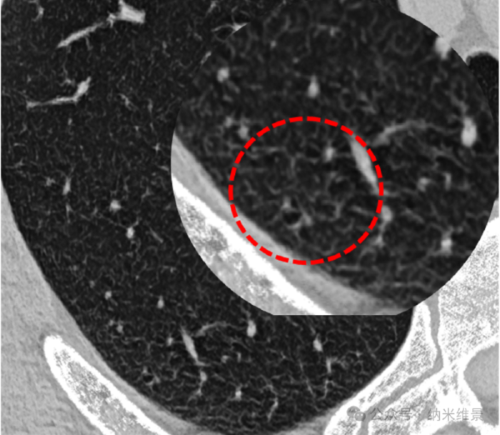

在临床肺中部成像,相控阵CT能更清晰地显示磨玻璃结节的分叶、毛刺、血管穿行等特征,对间质性肺病的叶间线、小叶内线等细微结构辨识度极高。

次级肺小叶在CT上的首次亮相

清晰呈现“看不见”的小气道

尤为重要的是,在慢性阻塞性肺疾病(COPD)的应用中,小气道(直径<2mm)的病变是COPD的早期改变,但以往方式无法清晰显示。

相控阵CT首次在体实现了高达11-13级支气管的清晰成像(常规CT约为7级),为COPD、细支气管炎、哮喘等小气道疾病的早期诊断和干预提供了更多有利依据。